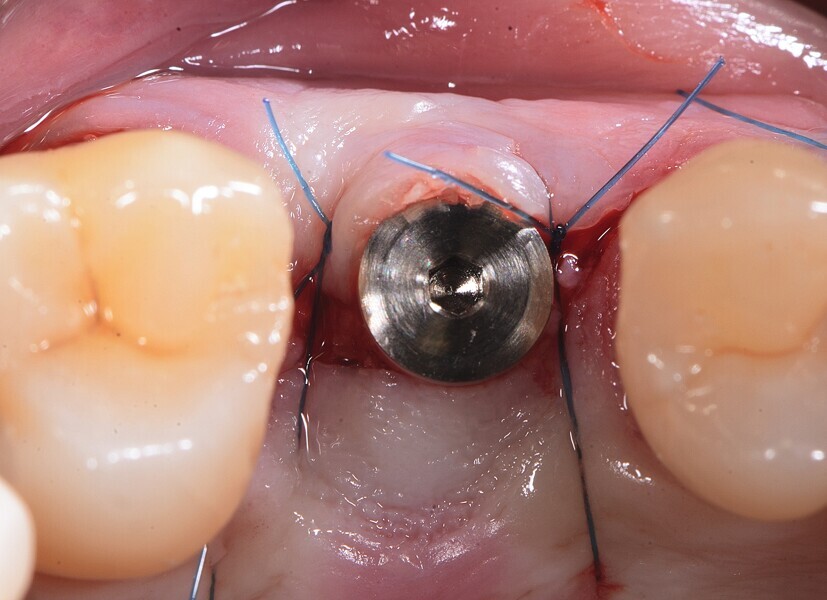

Fig. 6 : Insertion de l’implant.

Fig. 7 : Insertion de l’implant.

La première phase du traitement implantaire a consisté à extraire la dent et à préserver l’alvéole au moyen d’une allogreffe et d’une membrane de collagène. Six mois après, l’os régénéré a permis de procéder à la seconde phase du traitement comportant la pose d’un implant deux pièces en céramique (Figs. 1–11).